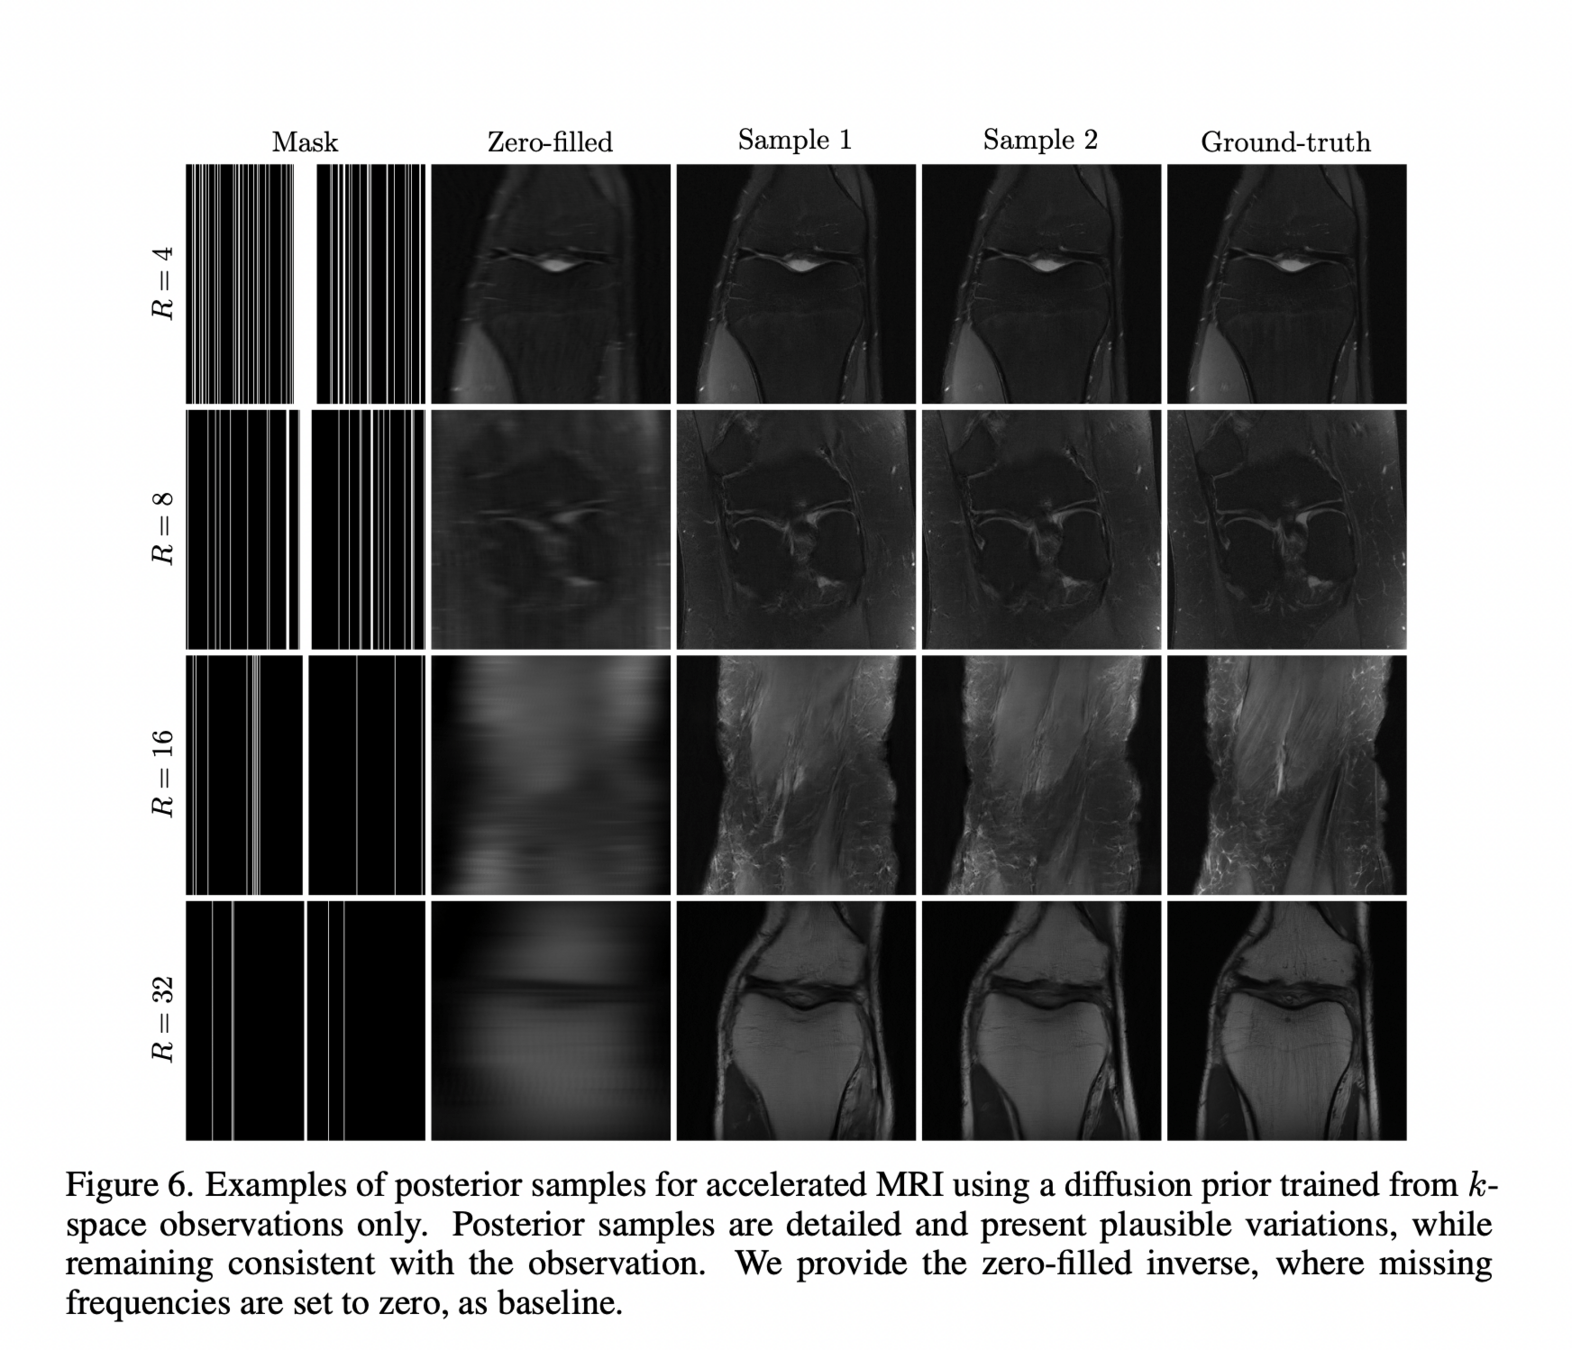

Generative Priors: Plug and Play

EHT posterior samples with different priors

["Event-horizon-scale Imaging of M87* under Different Assumptions via Deep Generative Image Priors" Feng et al]

CIFAR-10

GRMHD

RIAF

CelebA

(Sims)

(Sims)

(LR Natural Images)

(Human Faces)

Prior

Generative priors: learn directly?

Carolina Cuesta-Lazaro Flatiron/IAS - From Zero to Generative

["Learning Diffusion Priors from Observations by Expectation Maximization" Rozet et al]